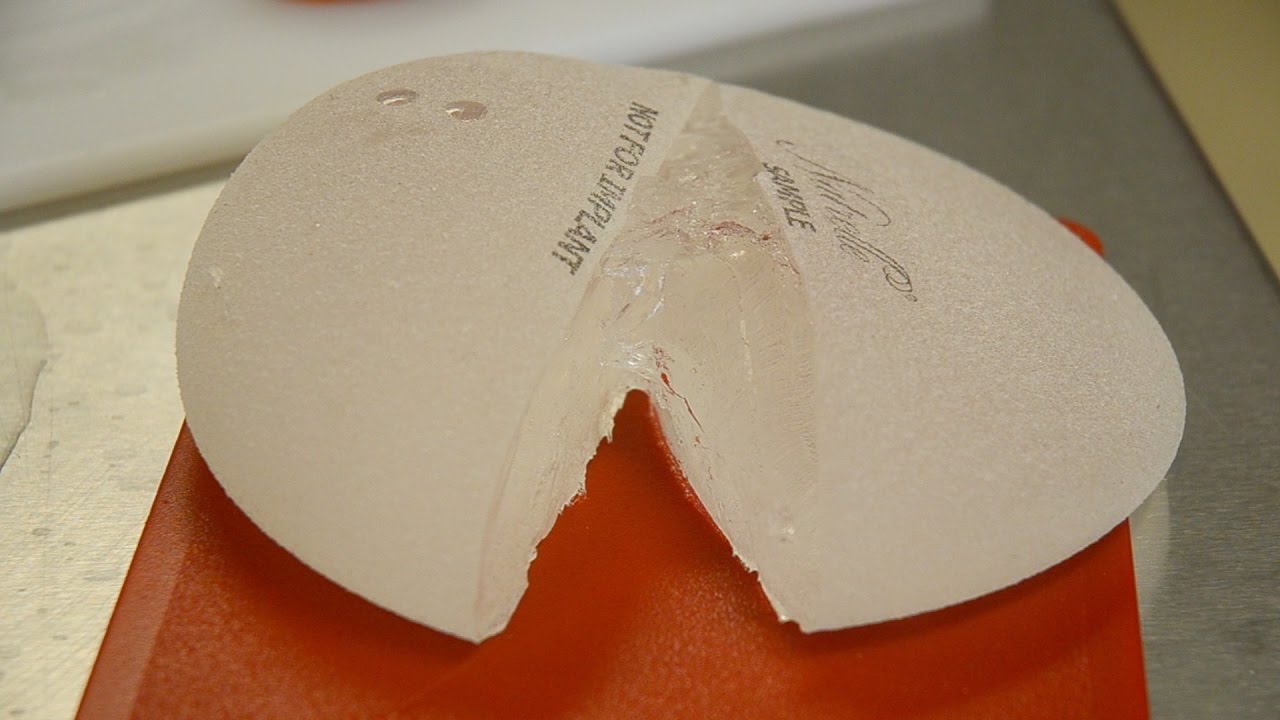

Анатомические импланты Eurosilicone

Раздел: Визуальный дайджест